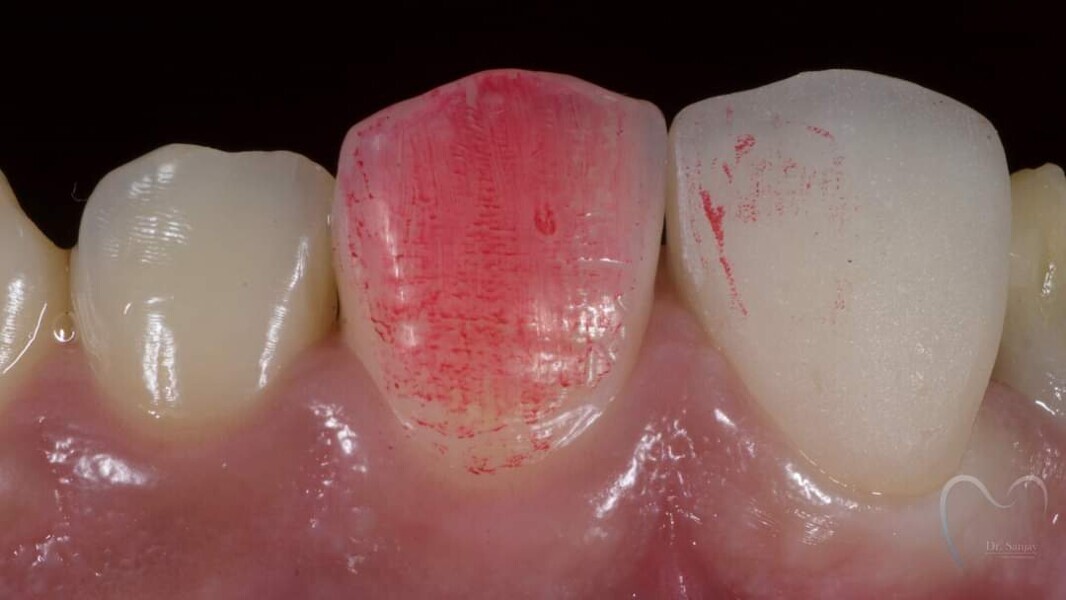

Esthetic Rehabilitation of Maxillary Anterior Teeth: Dr Sanjay Sah